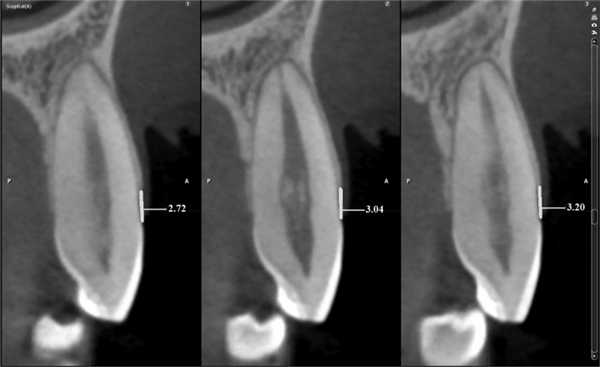

Рис. 5. Измерение расстояния от ЭЦГ до альвеолярного гребня в области зуба 2.3 (без рецессии). В данном случае показатели на 3 реформатах составили: 2,72; 3,04; 3,20 мм.

Медиана параметра «ЭЦГ — альвеолярный гребень» в области зубов, имеющих клинически определяемую рецессию, составила 5,8 [4,65; 7,24] мм. В контрольной группе этот показатель составил 4,47 [4; 4,7] мм (см. рис. 3). По данному показателю группы достоверно различались (p<0,05).

Для повышения точности исследования проводили 3 вестибуло-оральных реформата относительно центральной оси с шагом 0,5 мм.